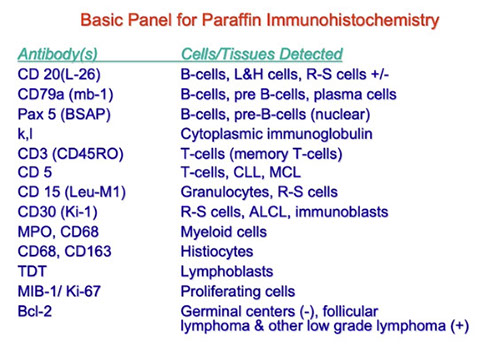

IHC: B cell markers (+ CD19/10/34/99, PAX5) nuclear TdT, HLA-DR, sometimes T cell markers (-/+ 13, 33, 117), 56

- PAX-5 is most sensitive/specific in B-LBL; CD20 is variable; CD79a is usually positive, but can cross react with T-LBL; CD10 and TdT are positive in most cases

IHC: (+) cytoplasmic CD3, CD2/ 99 (var) / 7, occasional NK / myeloid (CD13/33) markers, TdT nuclear, variable CD3 / 5 / 34 (var) / 10 / 1a / 45

IHC

(+) IgM/D2, CD5 (>3/4)/11c/19/20 (dim) / 22/23/43/79a, Bcl-2, PAX5

- neg: CD10/79b/81, FMC7 (dim to neg), cyclin D1 (Bcl1)